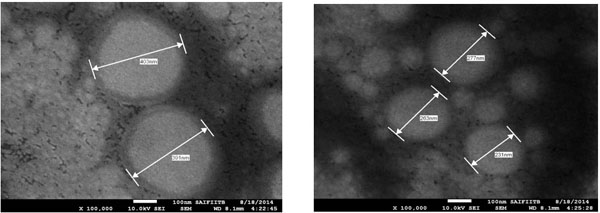

5.6.4. Scanning Electron Microscopy (SEM)

SEM photographs (Fig. 9) showed that the prepared niosome exhibited smooth surface with nano size dimension and were homogenously distributed. The diameter of the prepared niosome was in range of 231- 403 nm when seen through electron microscope.